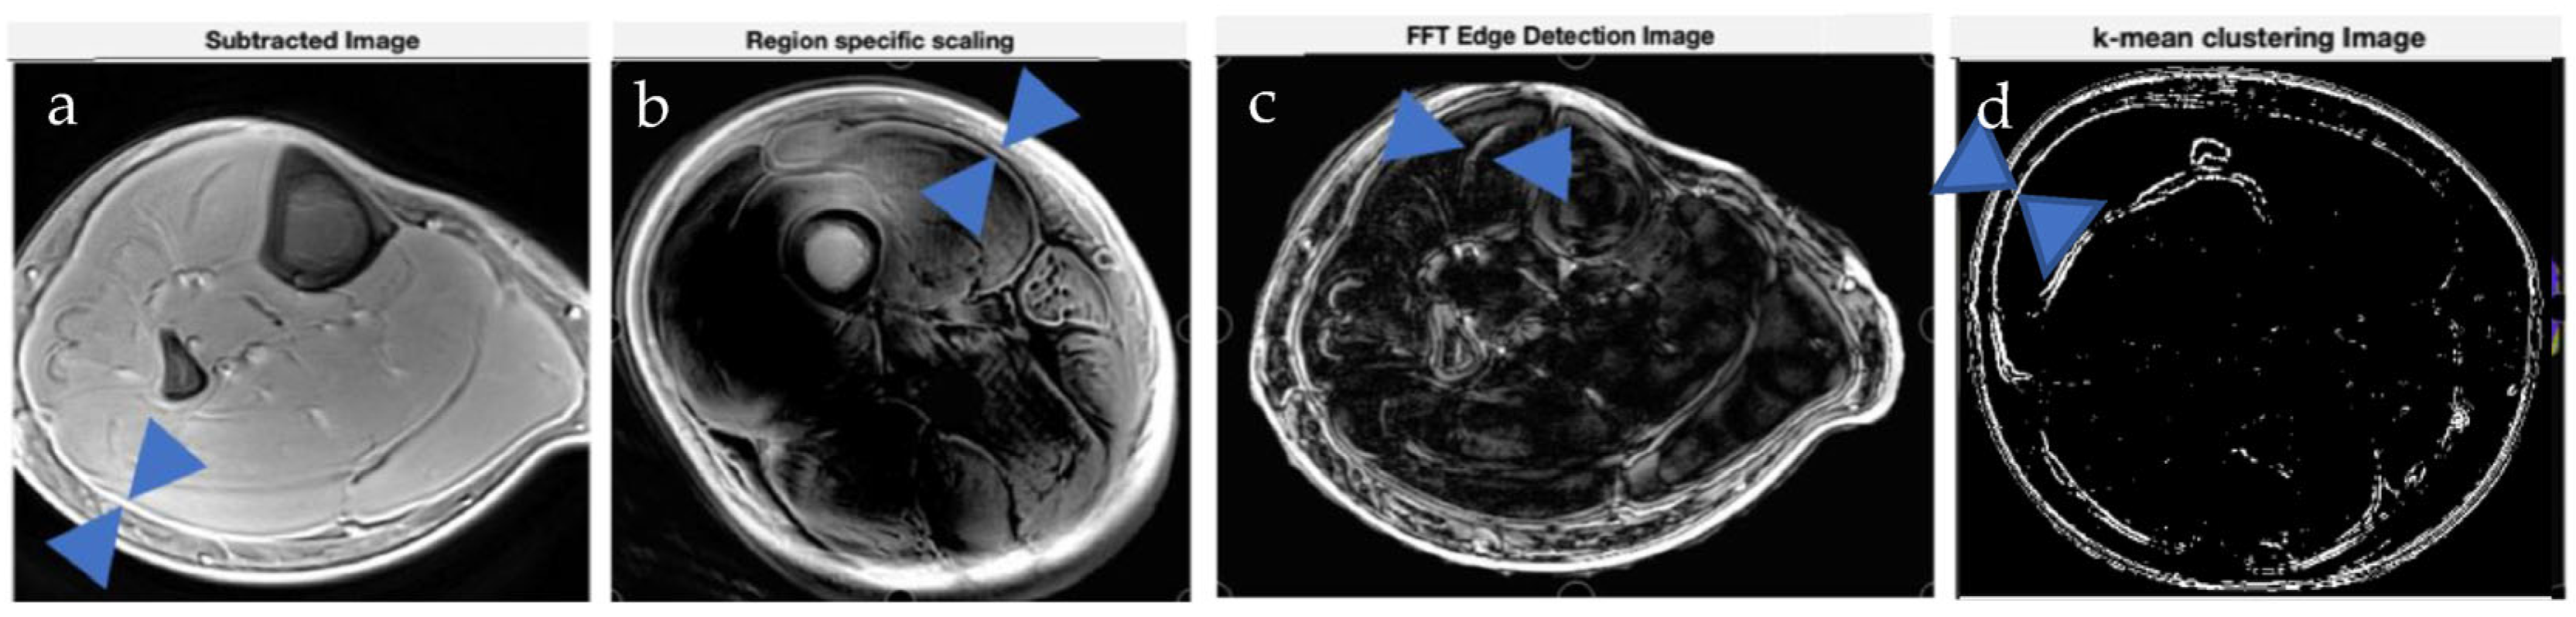

3.2. Image Processing Method Results

Results from image processing methods reveal enhanced contrast for deep fascia tissue in the lower limb from region-specific scaling, intensity images, Weiner filters, edge detection using FFTs, watershed, and K means clustering (Figure 5, Figure 6 and Figure 7). In cases where deep fascia is not detectable due to insufficient contrast, these methods may be used to enhance contrast for deep fascia identification, segmentation, or geometrical measurement (e.g., thickness). We found that region-specific scaling improved SNR by 65% (Figure 7).

Figure 6.

Image processing techniques demonstrate enhanced contrast for deep fascia identification. Blue markers on the images show deep fascia locations. (a) Subtraction of the short echo time image from the ultra-short echo time image reveals deep fascia on the periphery of the muscle using a 3D Cones sequence. (b) Region-specific scaling on image from (a) enhances deep fascia–muscle contrast. (c) Application of the Weiner filter improves contrast. In subfigures (d–f), the ROI—in this case, deep fascia—was extracted from the images. (d) Edge detection algorithm based on FFT on preprocessed 3D spiral VIBE image filters out deep fascia within muscle. (e) Watershed algorithm used to segment the features using unsupervised learning; in this case, the deep fascial layers. (f) K-Means clustering highlights deep fascia regions as well (shown here in the black channel).

Figure 7.

Illustration of image processing methods applied to various connective tissues. Blue markers indicate the locations of the deep fascia and aponeurosis, which are manually annotated to help the reader easily identify the relevant tissues. (a) Image subtraction reveals high-signal, high-contrast images of deep fascia abutting the periphery of the muscle. (b) Region-specific scaling enhances deep fascia–muscle contrast. (c) Edge detection algorithm on 3D spatial image reveals aponeurosis within muscle. (d) K-Means clustering highlights the deep fascia region, shown in blue.